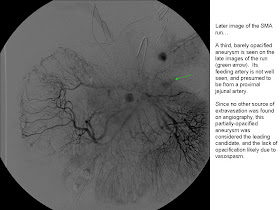

| 46 year-old male with known polyarteritis nodosa and new hemorrhage. (Courtesy Dr. D. Eschelman) |

Case courtesy of Dr. Dave Eschelman, Thomas Jefferson University Hospital